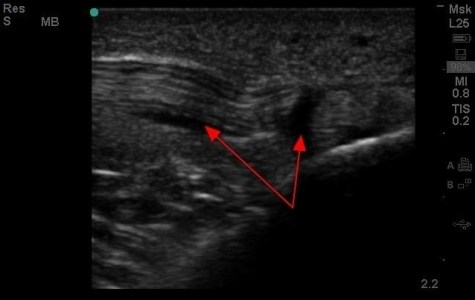

SonoCase: Had this athlete who had knee pain, tough to walk, slight effusion – sent for an arthrocentesis by the PCP to rule out septic joint…..but, he was worried he had an ACL tear, but upon looking with US around his patellar tendon (where he was tender), we got the diagnosis in a flash. The linear probe was used by Dr. Brita Zaia to visualize the linear echoes of the tendon in longitudinal axis – fluid is seen around the thickened tendon which usually is not there. Too bad US didnt exist in the times of Troy….Ah, the truth truly is in the ‘sound.